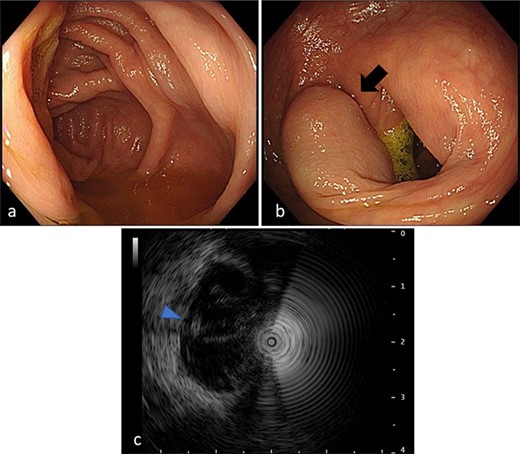

A 50-year-old man was examined at a local hospital for an annual check-up, and colonoscopy revealed an SMT-like lesion near the ascending colon. Due to this finding, the patient was referred to our hospital for further testing and treatment. He had no significant medical history or abnormal laboratory data, and physical examination findings were unremarkable. Colonoscopy confirmed the presence of SMT-like lesion in the ascending colon, while the cecum and Bauhin valve appeared normal. A cystic lesion in the intestinal wall was discovered on endoscopic ultrasonography (Fig. 1). Contrast-enhanced computed tomography (CT) also revealed the same lesion near the ascending colon, measuring 15 mm in diameter, with unclear continuity and no evidence of swollen lymph nodes (Fig. 2). Based on these findings, our preoperative diagnosis was an ascending colon SMT. Differential diagnoses included an appendiceal tumor and colon cancer. We planned to dissect the tumor for definitive diagnosis and treatment. However, endoscopic submucosal dissection is difficult for differential diagnoses.

CT image. An iso-density lesion in the ascending colon (arrowhead).